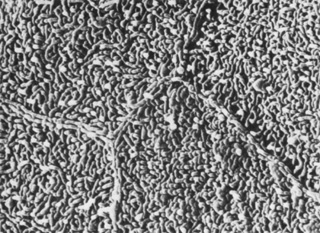

The human corneal endothelium is a single layer of 400,000 to 500,000 cells. Confocal microscopy provides views of this cell layer that surpass the details seen under specular microscopy (Figs. 19 and 20). Cells are 4 to 6 μm in height and 20 μm in width, and their posterior surfaces are predominantly hexagonal when viewed under specular microscopy (Fig. 21). Cross-sectional views with electron microscopy show that cell lateral walls are extremely tortuous and interdigitate with extensive folds and finger-like projections. It has been estimated that the total paracellular path length may be 10 times longer than the total height of the cell.90 Numerous gap junctions along the lateral membranes provide cell-to-cell cytoplasmic communication as evidenced by the presence of connexin 43 and the spreading of fluorescent dye from an injected cell to surrounding cells (Fig. 22).91

Fig. 21. Scanning electron micrograph of corneal endothelium. Note the regular hexagonal arrangement of the cells (1,170×). (Courtesy of Drs. Rodrigues, Waring, Hackett, and Donohoo.)

Fig. 22. Scanning electron micrograph of endothelial cell intracellular junctions (8,100×). (Courtesy of Drs. Rodrigues, Waring, Hackett, and Donohoo.)